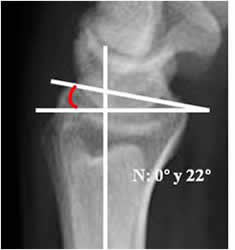

La inclinación volar:

Trazado en la Rx lateral. Angulo formado entre la perpendicular al eje del radio y una línea que une su extremo anterior y posterior. El valor normal es entre 0 y 22º (12). Cualquier valor negativo es patológico. (13). (Fig 49 y 50).

Fig 49. Inclinación volar.

Rx lateral de muñeca. Angulo formado entre la perpendicular al eje del radio y una línea que une la parte anterior y posterior del radio distal.